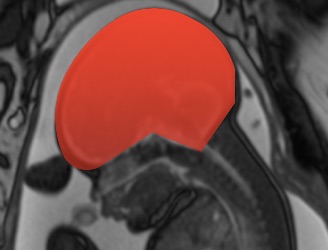

Pelvik ultrason, alt karın bölgesindeki (pelvis) organları değerlendiren güvenli ve radyasyon içermeyen bir görüntüleme yöntemidir. Üç farklı yaklaşımla uygulanabilir:

Transvajinal Ultrason (Vajinadan): Vajinal yoldan yapılan, rahim ve yumurtalıkları daha ayrıntılı gösteren yöntem.

Hastanın sırtüstü yattığı bu incelemede, karın bölgesine özel bir jel uygulanır. Jel, ses dalgalarının cilde iletimini kolaylaştırır. Prob, karın üzerinde gezdirilerek görüntüler elde edilir.

Hastanın mesanesi boşken yapılan bu incelemede, vajinaya ince ve steril kaplı bir prob yerleştirilir. Probun hareketiyle rahim, yumurtalık ve çevresel dokular daha yakından görüntülenir.

Bu özel ultrason türü, rahim ve yumurtalıklardaki kitlelerin kanlanma özelliklerini değerlendirmemizi sağlar. Özellikle tümöral yapılar genellikle fazla kanlanma gösterir. Bu yöntem, şu amaçlarla uygulanır:

Rahim duvarı kalınlaşmaları (endometrial hiperplazi), polip, myom, yumurtalık kistleri detaylı incelenir.